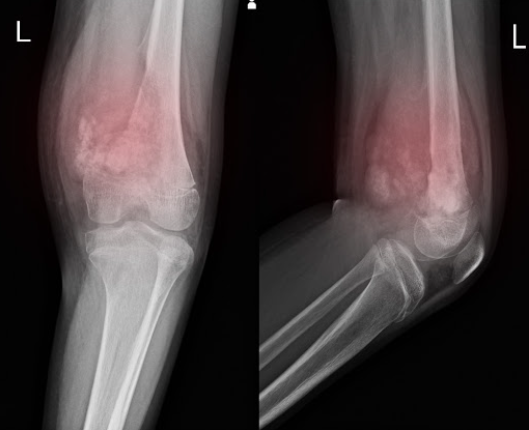

Geralmente, o tumor aparece nos ossos longos, como o fêmur, a tíbia, especialmente perto do joelho, e o úmero, próximo ao cotovelo. Cerca de 80% dos casos estão ligados ao fêmur.

Como o osteossarcoma afeta, na maioria dos casos, os ossos das pernas, o principal sintoma costuma ser dor na região afetada.

“Dor nos ossos persistente e contínua, que se estende para dor noturna, às vezes acordando a criança por conta da dor é característica que já gera uma desconfiança”, alerta o médico.